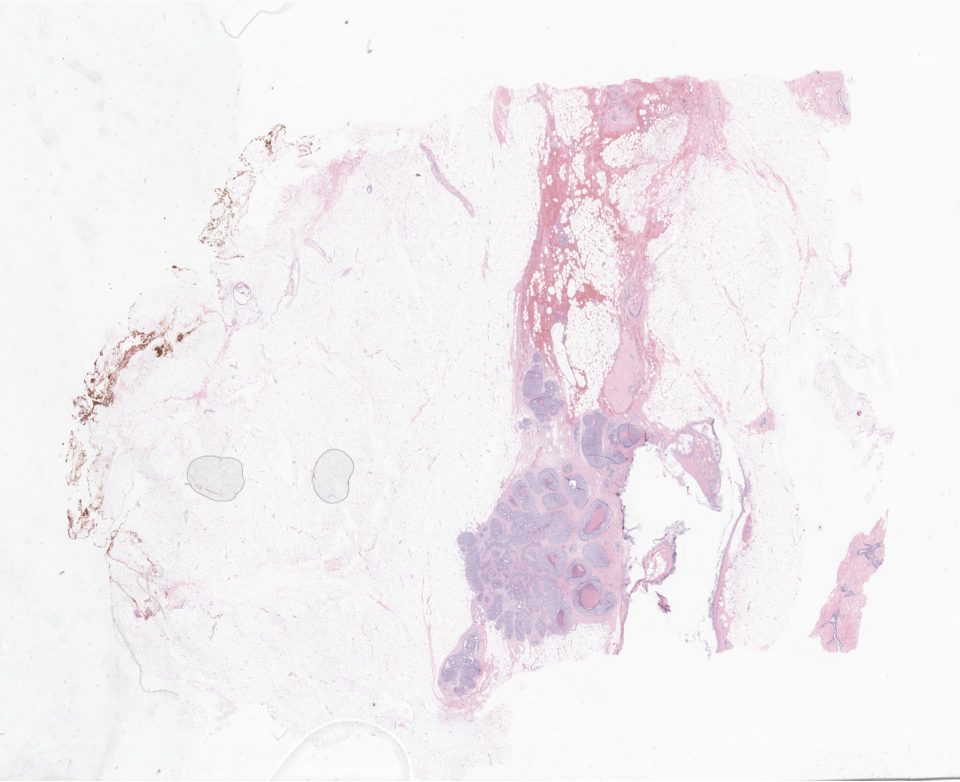

09998f43-9418-146e-288a-5dabbe127ff1_151107.svs

103868

x

84553

@

40X